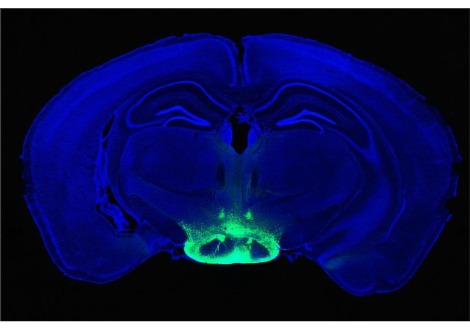

تم تسليط الضوء على التلفيف المجاور للحصين، وهو يتقلص لدى الأشخاص الذين فقدوا الكثير من أسنانهم

وبعد مراعاة عوامل مثل العمر والجنس ومستوى التعليم ، لم يجد الباحثون أي ارتباط بين فقدان الأسنان وحجم الدماغ لدى جميع المشاركين . ومع ذلك، عندما ركزوا فقط على أولئك الذين لا يعانون من ضعف إدراكي، وجدوا بعض الأنماط الموحية . أولئك الذين لديهم أقل من 10 أسنان كان لديهم، في المتوسط، حجم أقل بنسبة 3.5% في منطقة تسمى التلفيف المجاور للحصين، مقارنة بأولئك الذين لديهم أكثر من 24 سنًا . كما كان لديهم أيضًا زيادة بنسبة 25% تقريبًا في الآفات في المادة البيضاء في الدماغ ، وهي حزم من الألياف العصبية التي تربط مناطق الدماغ المختلفة .

تظهر هذه التغيرات الدماغية لدى الأشخاص المصابين بالخرف أيضًا . وهذا ليس مفاجئًا نظرًا لأن التلفيف المجاور للحصين يلعب دورًا في استرجاع وترميز الذكريات بينما تساهم آفات المادة البيضاء في التدهور المعرفي .